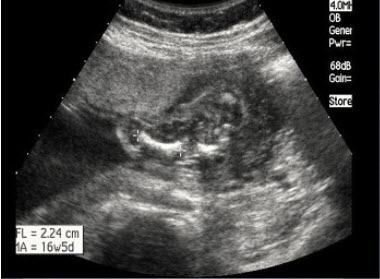

26、单项选择题

24周胎儿股骨超声检查如图,最可能的诊断是()

A.致死性骨发育不全

B.内翻足

C.羊膜带综合征

D.骨硬化症

E.并指(趾)畸形